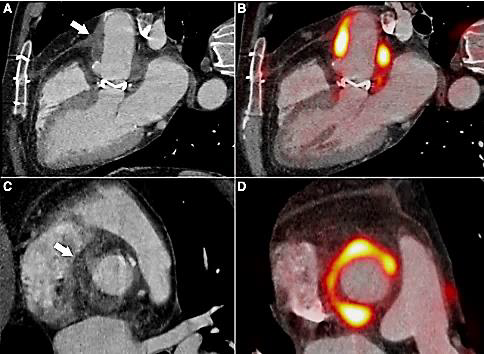

Culturas de escarro, de sangue e de urina coletadas na admissão e antes da antibioticoterapia resultaram negativas. Solicitado ecocardiograma transtorácico que demonstrou válvula normofuncionante sem outras alterações, achado este confirmado por um ecocardiograma transesofágico posteriormente. Durante evolução na enfermaria, paciente passou a queixar-se de fraqueza em todo o hemicorpo esquerdo, sendo prontamente encaminhado à tomografia computadorizada de crânio que não demonstrou alterações. Paciente recuperou espontaneamente a força cerca de quatro horas após. Diante da principal suspeita, foi solicitado o exame demonstrado na Figura 8.

--------------Figura 8. Tomografia por emissão de pósitrons do coração

Assinale a alternativa que apresenta o diagnóstico mais provável e qual o esquema antibiótico empírico ideal para este paciente.